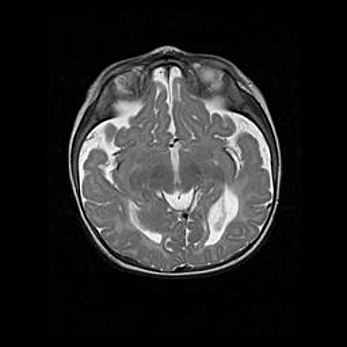

Наружная гидроцефалия с возможной атрофией височных областей.

Возраст: 28 дней

Вес: 3670 г

Пол: мужской

Окружность головы: 38 см

Срок гестации: 40 недель

Гидроцефалия головного мозга у новорожденных – это заболевание, которое характеризуется скоплением избыточного количества спинномозговой жидкости в желудочковой системе головного мозга в результате затруднения её перемещения от места выработки к месту поглощения в кровеносную систему или вследствие нарушения абсорбции. При открытой наружной форме гидроцефалии у новорожденных расширяются и переполняются субарахноидные пространства.

При нормотензивных  формах,  которые,  как  правило,  являются  следствием  перенесенных ишемических  повреждений  паренхимы  мозга,  возможно  сочетание микроцефалии  с нормотензивной гидроцефалией. В основе данных изменений лежит атрофия больших полушарий с преимущественной  локализацией  в  лобно-височных  областях.